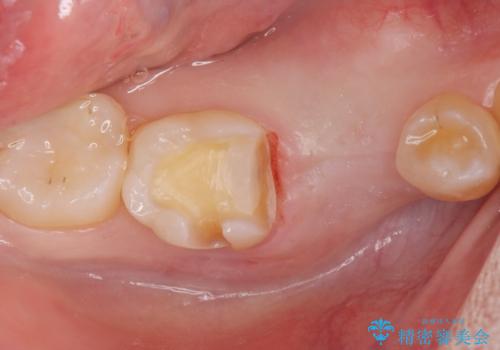

併用して銀歯も気になるとの事でしたのでセラミック治療も行いました。

- インプラント体、アバット、仮歯、ジルコニアクラウン・42.9万円 e-maxインレー・7.7万円 費用は治療当時の料金となります

適合の良いセラミックが入りました。